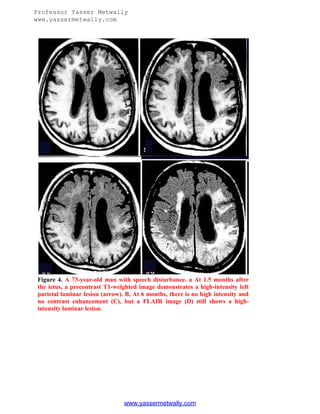

Figure 4. A 73-year-old man with speech disturbance. a At 1.5 months after

the ictus, a precontrast T1-weighted image demonstrates a high-intensity left

parietal laminar lesion (arrow). B, At 6 months, there is no high intensity and

no contrast enhancement (C), but a FLAIR image (D) still shows a highintensity laminar lesion.